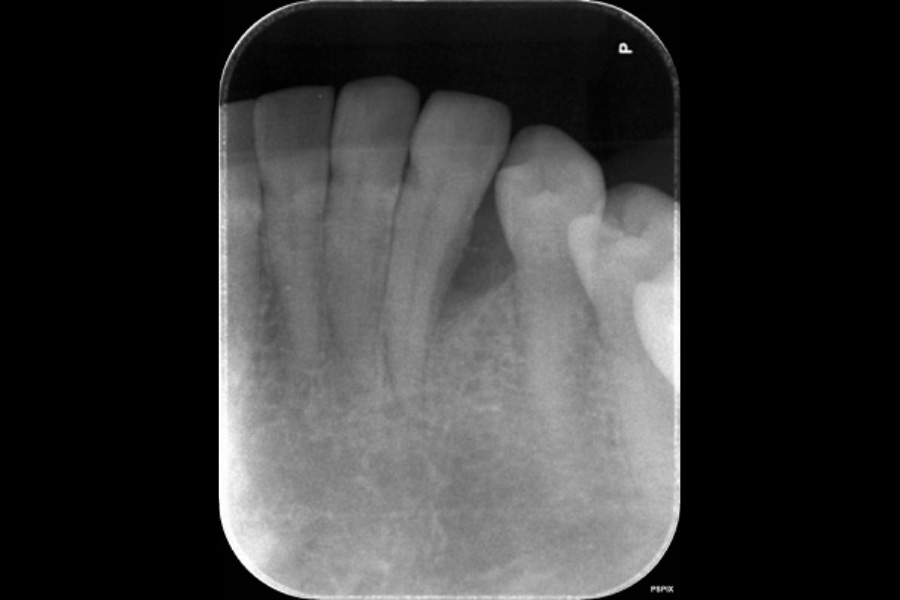

左下奥歯の歯ぐきから出血する

【歯周組織再生療法】

- 主訴

- 左下奥歯の歯ぐきから出血する

- 治療内容

- 左下6遠心に縁下歯石と垂直性骨吸収が認められたためエムドゲインと骨補填材を用いて歯周組織再生療法を行った

- 治療に伴うリスク

- 歯肉退縮、知覚過敏